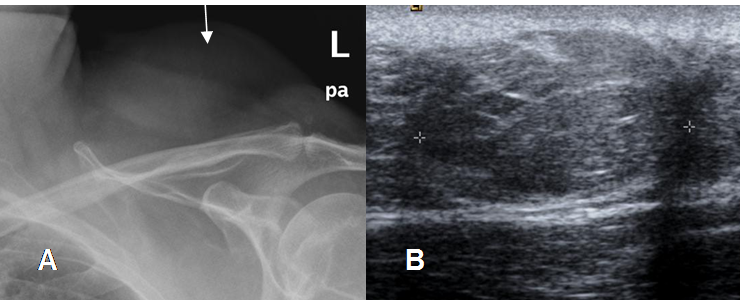

Fig 158. Lipoma.

A: Rx AP y B: Ecografía. Masa de tejidos blandos en la región deltoidea, con imagen sólida, bien definida e isoecoica por lipoma.